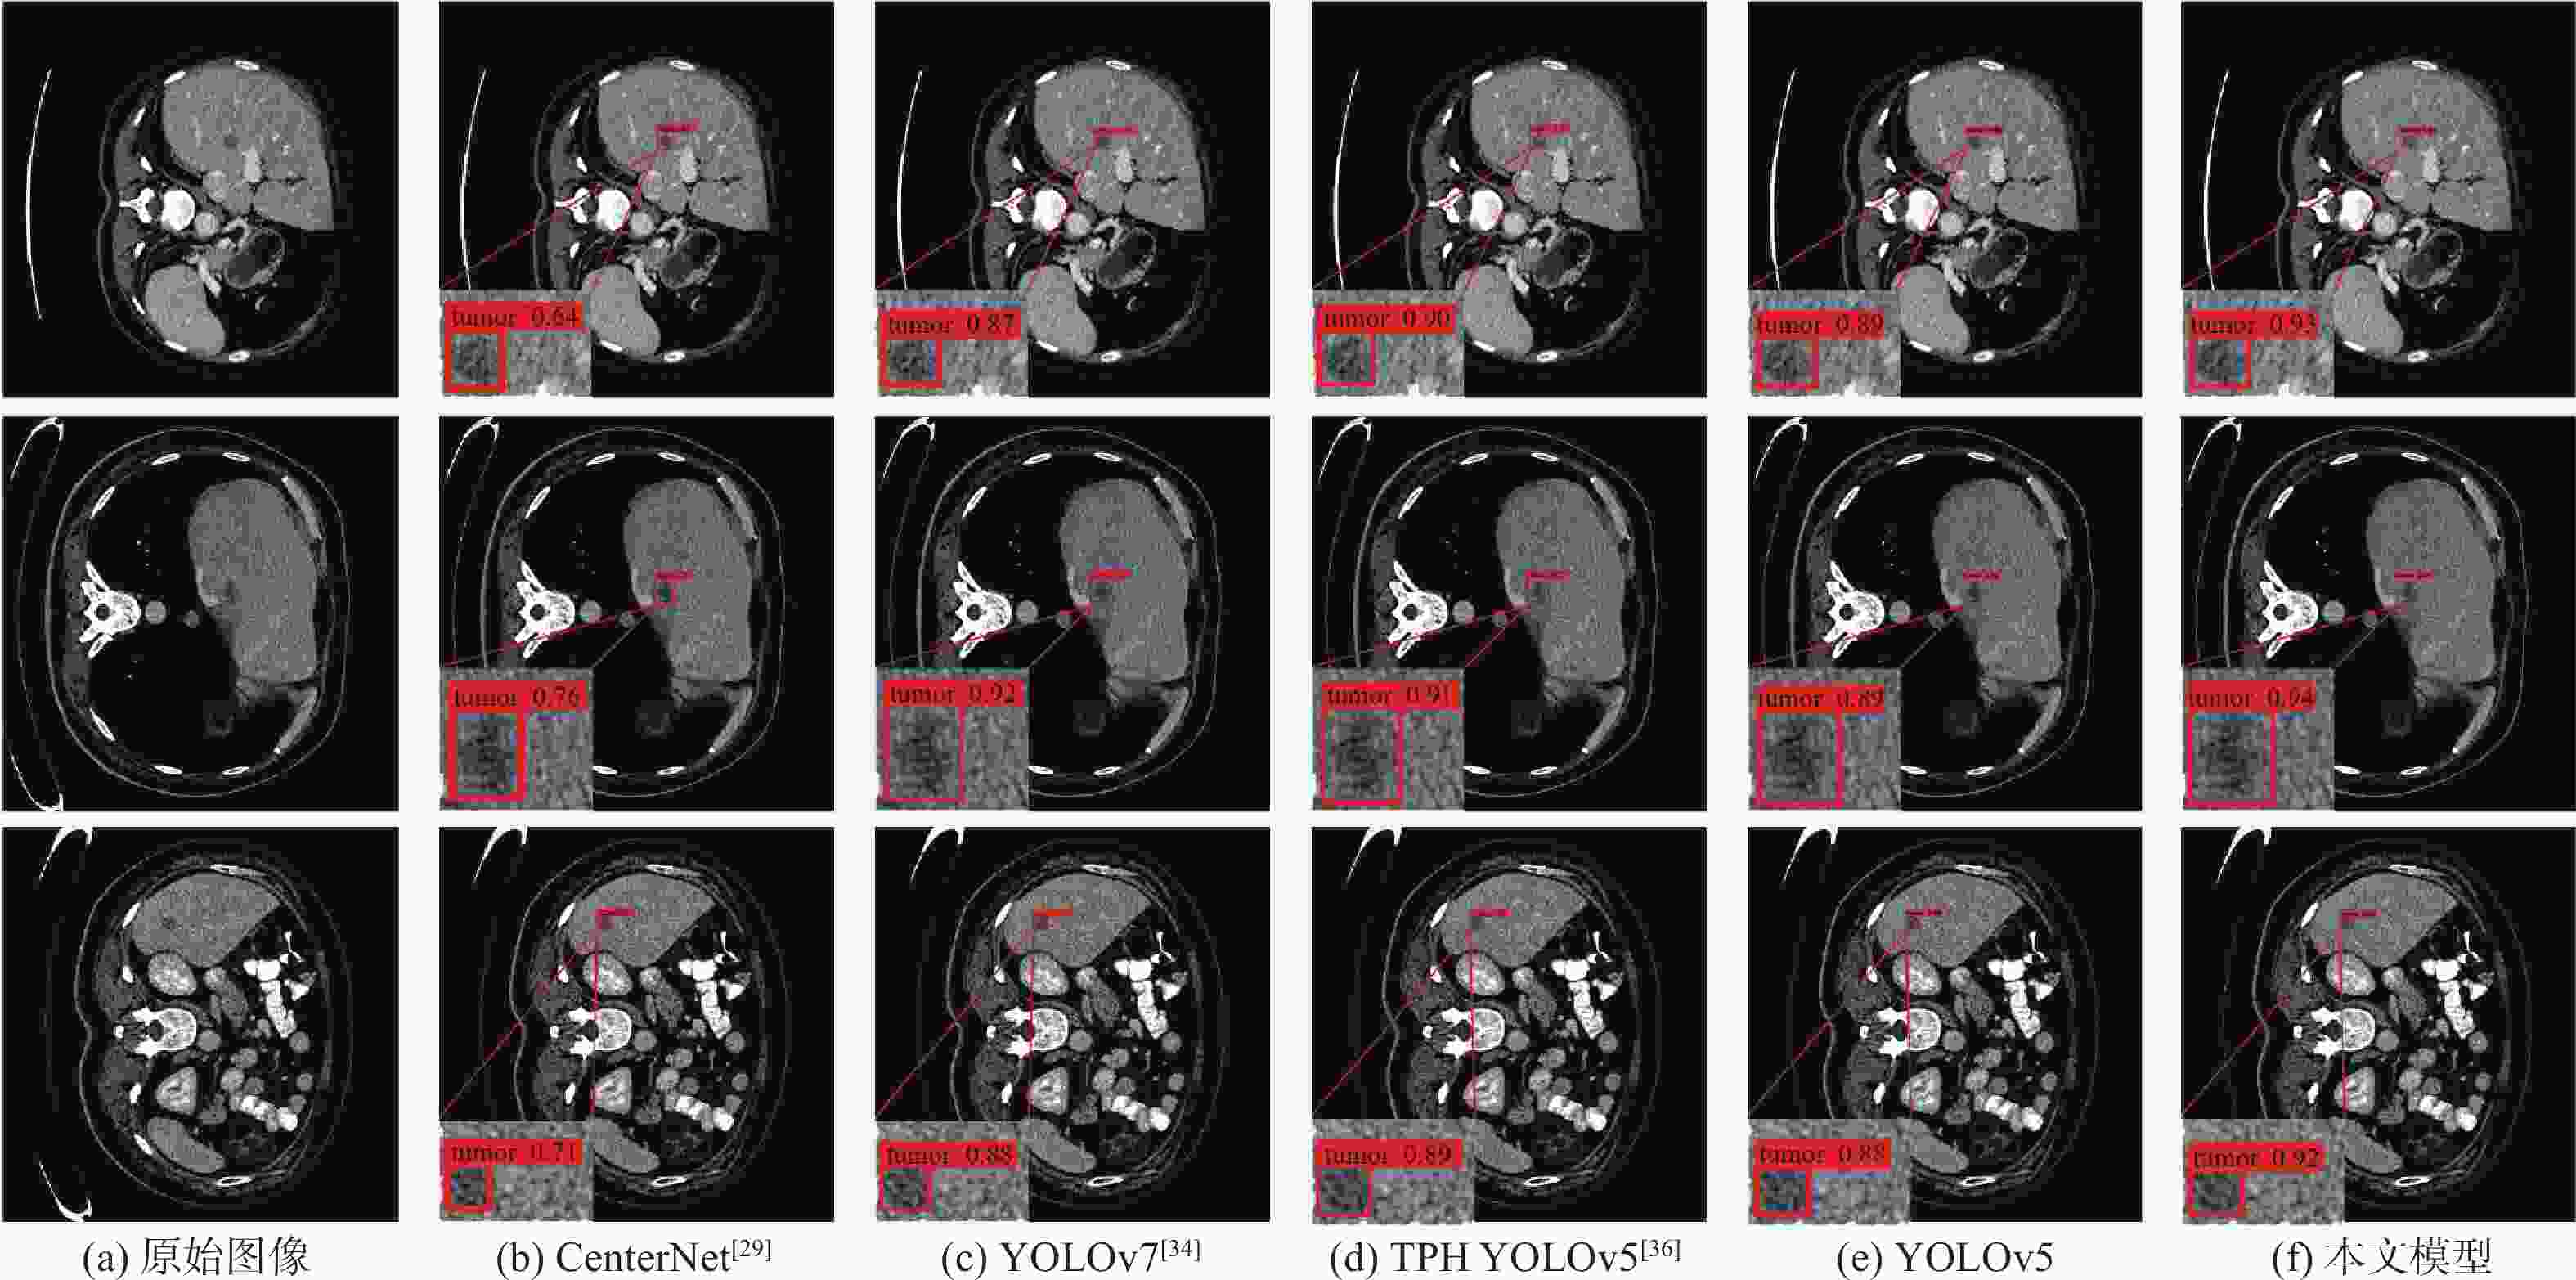

针对肝脏肿瘤检测中多尺度特征表达能力不足的问题,提出一种融合重参数化卷积、加权双向特征金字塔和注意力机制的肝脏肿瘤CT图像检测方法。使用数据增强改善样本量较少的问题,提高模型的泛化能力;使用加权双向特征金字塔网络融合图像的浅层与深层特征,提高多尺度特征的提取能力;在特征融合中引入无参数平均注意力模块,关注肝脏肿瘤的关键特征;使用重参数化卷积和边界框(SIoU)损失函数提高肿瘤的检测和定位能力。实验结果表明:所提方法在LT3DM和LiTS2017数据集上的平均精度均值(mAP)分别达到了92.9%和92.2%,比YOLOv5模型提高了2.3%和1.8%,相较于主流检测模型,所提方法具有更好的肝脏肿瘤检测能力。

Abstract:To address the problem of insufficient multi-scale feature representation in liver tumor detection, we propose a liver tumor CT image detection method that integrates reparameterized convolution, weighted bidirectional feature pyramid, and attention mechanism. Firstly, data augmentation is used to improve the problem of small sample size and enhance the generalization ability of the model. Secondly, to enhance the ability to extract multi-scale features, the weighted bidirectional feature pyramid network is utilized to merge the image's shallow and deep features. Then, a parameter-free attention mechanism is introduced in feature fusion to focus on the key features of liver tumors. Finally, reparameterized convolution and shapeaware intersection over union (SIoU) loss functions are used to improve tumor detection and localization accuracy. The mean average precision(mAP)of this method on LT3DM and LiTS2017 datasets reached 92.9% and 92.2%, respectively, which is 2.3% and 1.8% higher than that of the YOLOv5 model. The experimental results indicate that this method has a greater ability to detect liver tumors than standard detection models.

模型 P/% R/% F1/% mAP/% 参数量 浮点运

算速度/

109 s−1SSD512(VGG) [27] 93.1 62.5 74.7 84.3 23.75×106 87.55 YOLOv3[28] 88.7 73.9 80.6 82.9 61.52×106 49.68 CenterNet[29] 92.8 82.5 87.3 88.6 32.66×106 35.09 EfficientDet[30] 62.5 63.9 63.2 63.5 3.83×106 2.37 YOLOv4[32] 82.4 55.2 68.0 67.6 63.94×106 45.41 Faster R-CNN(Res50) [31] 39.4 71.8 50.9 62.2 28.28×106 241.71 YOLOX[33] 91.5 85.8 88.5 89.9 8.94×106 8.56 YOLOv7[34] 92.8 82.2 87.2 89.6 6.22×106 33.01 YOLOv5 93.6 85.7 89.4 90.6 7.02×106 15.90 PP PicoDet[35] 86.1 71.2 77.9 80.5 1.18×106 4.59 TPH YOLOv5[36] 94.2 86.9 90.4 90.9 40.82×106 36.26 YOLOv8 80.1 93.3 87.0 88.1 11.13×106 9.10 FCOS[37] 91.9 80.1 85.6 88.1 32.11×106 51.56 DETR[38] 59.8 81.3 68.9 71.7 36.74×106 23.81 MAEfficientDet-D0[7] 86.2 84.1 80.9 85.6 4.34×106 2.83 MAEfficientDet-D1[7] 86.8 84.8 85.1 86.5 7.08×106 6.81 本文模型 94.6 88.3 91.3 92.9 7.17×106 16.30 表 7 不同模型在LiTS2017上的检测性能对比